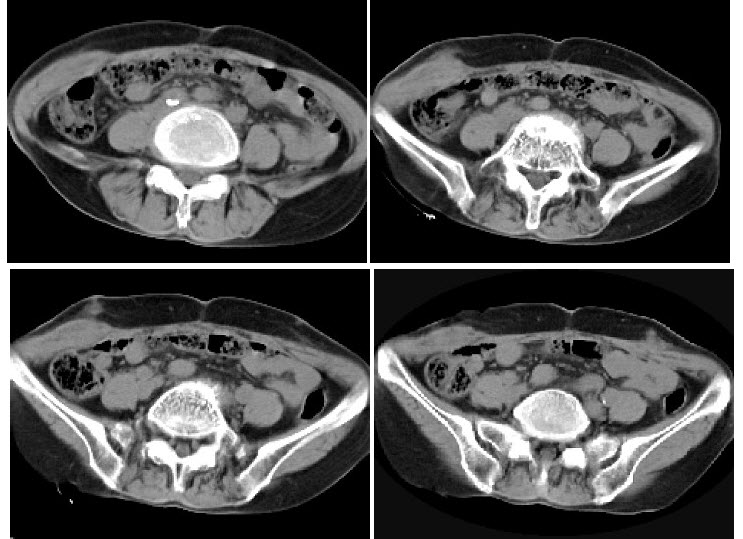

女,57岁,右侧下腹壁逐渐增大性包块1年余,无发热,偶有疼痛,体检:右下腹壁触及一约7cm×8cm大小、质硬包块,活动度差,局部皮肤无红肿,CT表现如图,最可能的诊断为()

正确答案:A